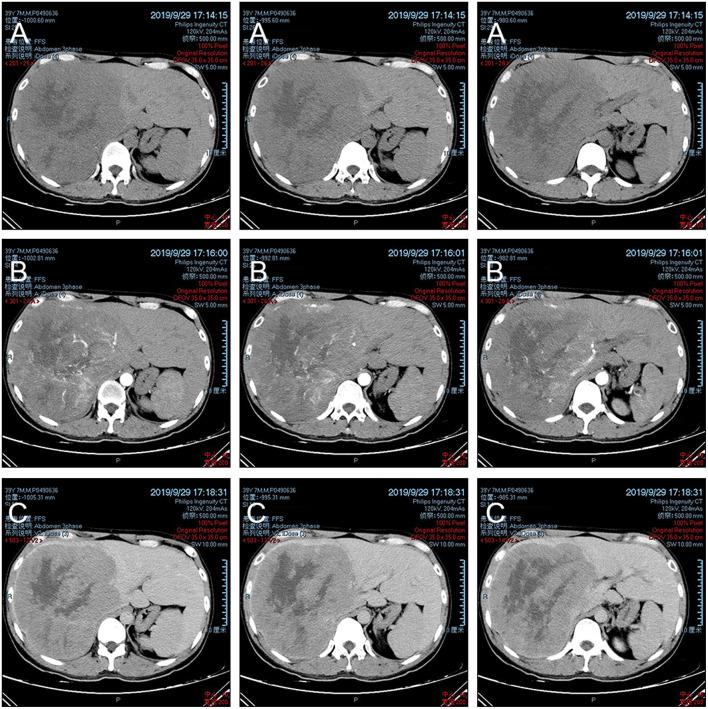

神经内分泌肿瘤是起源于神经内分泌系统的异质性恶性肿瘤。先前的研究表明,这种癌症类型主要位于胃肠道,且常转移至肝脏。原发性肝脏神经内分泌肿瘤非常罕见,而同时合并肝细胞癌(HCC)的原发性肝神经内分泌肿瘤(PHNET)极为罕见。据我们所知,仅发现少数PHNET病例,这使得其诊断困难。在此,我们报告了肝脏中最大的一例已报道的“具有欺骗性”的混合性神经内分泌-非神经内分泌肿瘤病变,旨在提高对该疾病的认识并改善其治疗。在此,我们报告一例术前误诊病例,该病例表现出肝细胞癌的临床特征且无肝外肿瘤。术后病理证实为混合性神经内分泌-非神经内分泌肿瘤。随后该患者接受了依托泊苷和顺铂为主的化疗。在6个月的随访中未观察到疾病复发。我们报告了一例非常罕见且容易误诊的病例,我们推测存在正在经历神经内分泌和肝细胞癌分化的“未分化细胞”,在此过程中一些肝细胞癌细胞表达神经内分泌特征。我们建议在该疾病的管理中进行适当的手术及术后铂类化疗。